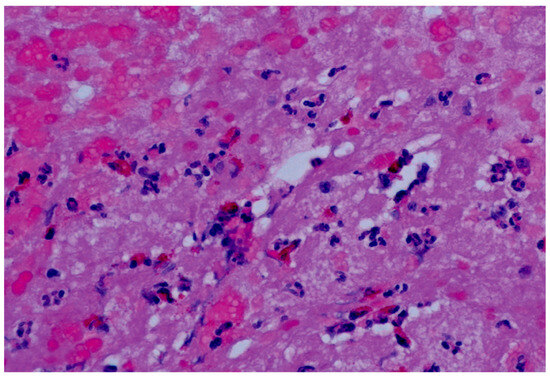

- Aretz, H.T.; Billingham, M.E.; Edwards, W.D.; Factor, S.M.; Fallon, J.T.; Fenoglio, J.J.; Olsen, E.G.; Schoen, F.J. Myocarditis. A Histopathologic Definition and Classification. Am. J. Cardiovasc. Pathol. 1987, 1, 3–14. [Google Scholar]

- Cooper, L.T.; Baughman, K.L.; Feldman, A.M.; Frustaci, A.; Jessup, M.; Kuhl, U.; Levine, G.N.; Narula, J.; Starling, R.C.; Towbin, J.; et al. The Role of Endomyocardial Biopsy in the Management of Cardiovascular Disease: A Scientific Statement from the American Heart Association, the American College of Cardiology, and the European Society of Cardiology. Endorsed by the Heart Failure Society of America and the Heart Failure Association of the European Society of Cardiology. J. Am. Coll. Cardiol. 2007, 50, 1914–1931. [Google Scholar] [CrossRef]

- deMello, D.E.; Liapis, H.; Jureidini, S.; Nouri, S.; Kephart, G.M.; Gleich, G.J. Cardiac Localization of Eosinophil-Granule Major Basic Protein in Acute Necrotizing Myocarditis. N. Engl. J. Med. 1990, 323, 1542–1545. [Google Scholar] [CrossRef]